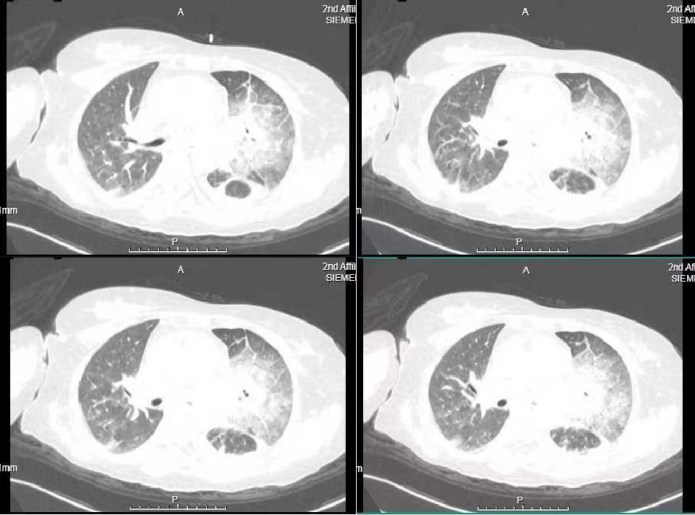

基于上述病史及基本检查,患者反复高热、呼吸困难,予以广谱抗菌药物后效果欠佳,我们考虑不能排除特殊病原体导致的重症肺炎,需积极寻找病原体,故完善纤支镜检查并送检肺泡灌洗液培养、宏基因组二代测序技术(mNGS)和组织活检等相关检查。纤支镜镜下见(图2):左主支气管分叉处狭窄,左肺各叶段黏膜见大量灰白色坏死物附着,至开口不同程度狭窄,气管结构破坏。mNGS提示小孢根霉相对丰57.95%,毛霉相对丰度41.75%。坏死物冰冻石蜡(图3)见真菌。肺泡灌洗液培养(图4)提示毛霉。显微镜下(图5)可见毛霉菌丝。

图2  左主支气管纤支镜下所见